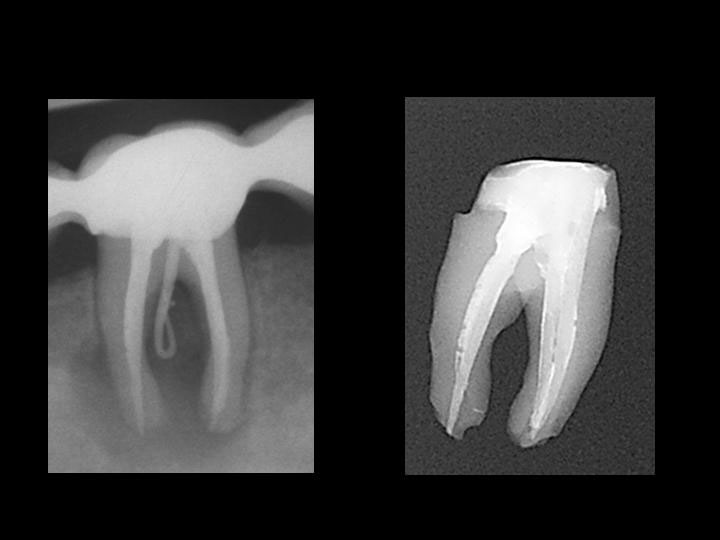

Unterer Molar mit Stripperforationen in der mesialen und distalen Wurzel als transparentes Präparat,

Röntgenbilder unmittelbar vor und nach Extraktion, Details der Wurzeln des extrahierten und gereinigten Zahns (Fotos Michael Arnold)

In den koronalen Bildanteilen erscheint die Wurzelkanalfüllung nicht überall

wandständig.